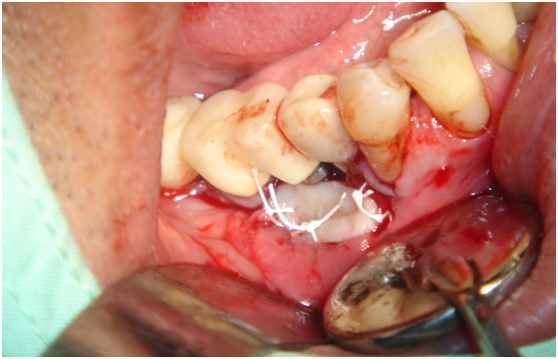

980305幫患者補角化牙齦並翻開清除發炎組織,期待能阻止繼續骨破壞

c. 由98/3補皮的臨床照片,推敲最初原本後面的三顆植體有可能放置在較頰側,但由於鄰接面有足夠的骨頭高度,所以牙齦仍被支撐在恰當位置,因此臨床上無特別發現;但當根裂拔牙後,鄰接面的高度一掉,很快地原本頰側骨頭不足的問題,便很快的浮現出來;接著螺紋跑出,而患者又是牙周病的高風險群,當時身體狀況不佳,口腔衛生照顧不足,都加乘造成骨破壞進一步進行。